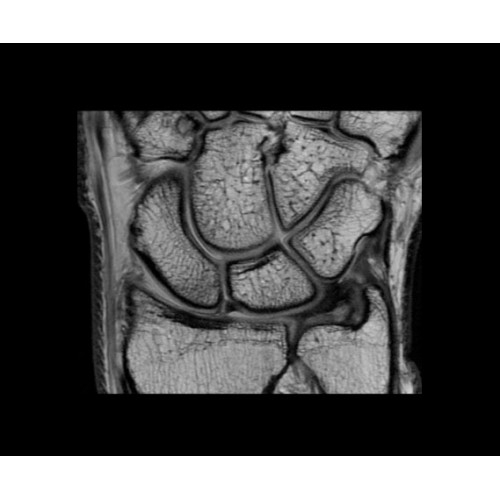

• OrthoWorks — программное решение для визуализации структур опорно-двигательного аппарата с прекрасным контрастированием тканей.

Поле обзора 50x50x50 см и апертура шириной 70 см позволят достоверно визуализировать сложные анатомические области для пациентов с крупным телосложением, например, плечи и бедра. Феноменальная однородность системы SIGNA Architect обеспечивает наиболее широкое поле обзора с улучшенными характеристиками градиентов. Ничто не останется незамеченным.

• Технология Digital Micro Switching (DMS)— это следующее поколение технологий радиочастотных катушек, основанное на замене аналоговых схем блокировки сверхбыстрыми микропереключателями (MEMS).

• Digital Surround Technology (DST)— это новая технология объемной оцифровки данных, которая объединяет сигналы от каждого элемента катушки. Прекрасное соотношение сигнал/шум и чувствительность поверхностных катушек в сочетании с превосходной однородностью и высокой проникающей способностью встроенной радиочастотной катушки — все это позволяет создавать качественные изображения не только позвоночника, но и всего тела.